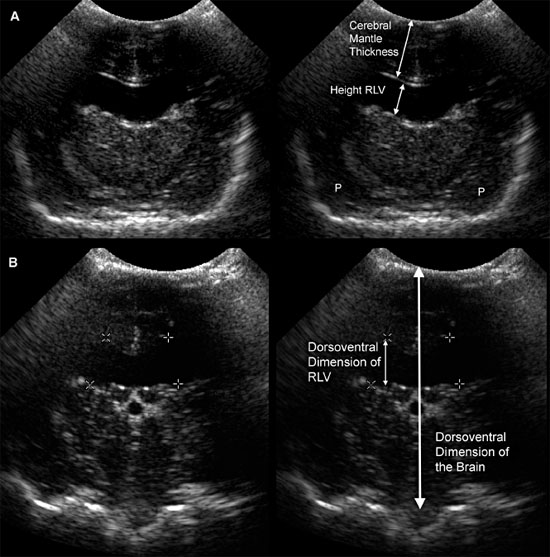

Figure 1.10. Measurement of the lateral ventricles in a 3-month-old Chihuahua. A: Transverse sonogram at the level of the interthalamic adhesion showing measurement using the method of Hudson et al. (1990) The lateral ventricular height can be compared with the cerebral mantle thickness (the thickness of the parenchyma dorsal to the lateral ventricle) to obtain the ventricle-mantle ratio. B: Transverse sonogram at the level of the pituitary gland showing measurement by using the method of Spaulding and Sharp (1990). Another method of measurement calculates the dorsoventral measurement of the lateral ventricle as a percentage of the dorsoventral measurement of the brain. RLV, right lateral ventricle.

Several methods have been proposed for evaluating enlarged lateral ventricles on sonograms (Figure 1.10 and Table 1.1). The degree of ventriculomegaly ranges from the ventricles being only slightly enlarged to ventricles occupying most of the brain. Midline structures between the lateral ventricles are intact in some animals, but the lateral ventricles become confluent in others (Figure 1.11).

Several studies using ultrasonography or magnetic resonance imaging (MRI) have shown that the severity of clinical signs is not directly related to the degree of ventriculomegaly, and ventriculomegaly can be seen in neurologically normal dogs (De Haan et al. 1994; Vullo et al. 1997). A study using MRI to compare ventricular volume in Yorkshire terriers to that in German shepherds indicated that percentage of ventricle area to hemispheric area was significantly greater in the Yorkshire terriers, but the range of ventricle area for neurologically normal Yorkshire terriers overlapped that of neurologically abnormal Yorkshire terriers (Estave-Ratsch et al. 2001). Ventriculomegaly should not be equated with clinically significant hydrocephalus (Hudson et al. 1990; Spaulding and Sharp 1990; Ettinger and Feldman 2005). Breed differences and severity of clinical signs should be considered. Measurement of blood flow in the basilar artery might help to identify animals in which enlarged ventricles are significant or are likely to become clinically significant (Saito et al. 2003). In one study, RI at the basilar artery was higher in dogs with clinical hydrocephalus or other brain disease compared with normal dogs or dogs with asymptomatic hydrocephalus. Additionally, asymptomatic dogs with severe ventriculomegaly and high RI later developed clinical signs, although the use of high RI by itself did not identify asymptomatic dogs that were likely to become symptomatic (Saito et al. 2003).